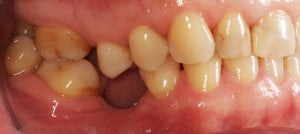

Do kliniki Stomatologia Bez Bólu zgłosiła się pacjentka, lat 61 z problemem nadwrażliwości zębów. Po przeprowadzonym wywiadzie stwierdzono spożywanie sporej ilości sezonowych owoców (truskawki, wiśnie, czereśnie, czarna porzeczka), nawet 3 razy dziennie. Następnie wykonano badanie wewnątrzustne. Stwierdzono obecność płytki nazębnej, ciemnego osadu oraz kamienia nazębnego na części trzonowców: